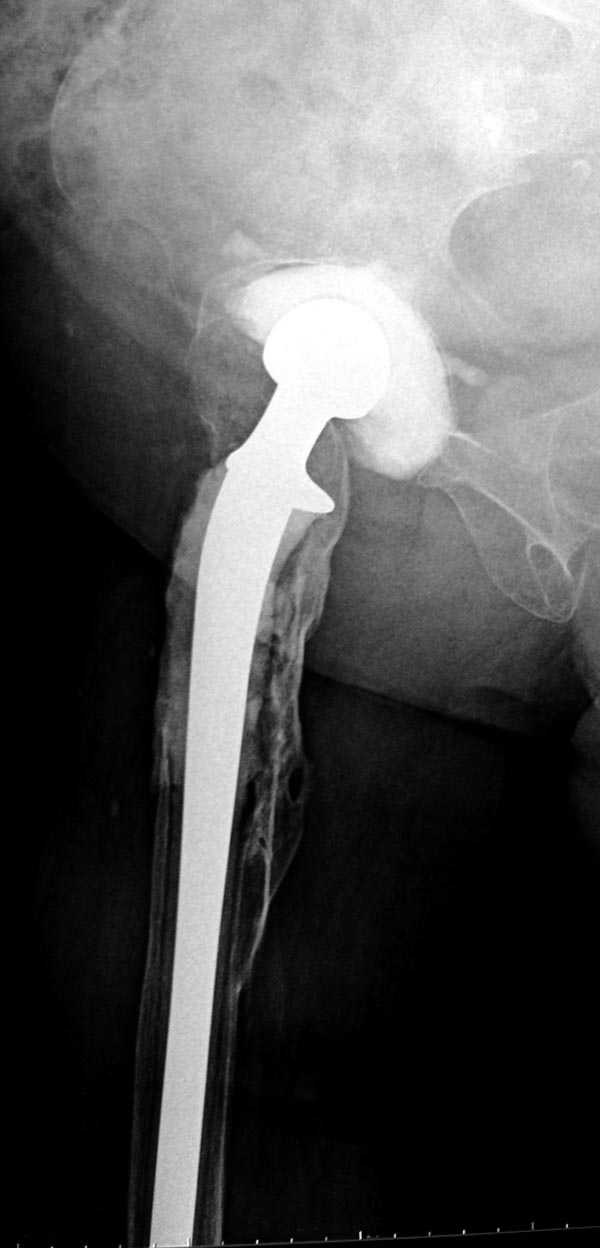

Вот снимки по свежей ситуации, парень 19 лет, длинный оскольчатый перелом бедра от шейки до в-с/3. давно уже ходит на своих ногах.

Представленные Вами рентгенограммы действительно являются примером качественной фиксации спице-стержневым аппаратом. Они, как ни что другое, многое иллюстрируют.

Кроме того, было бы ошибкой ставить знак равенства между нашим и Вашим пациентами. Они не только не похожи, разница между ними просто огромная. Говорю это не для того, чтобы задеть Вас или обидеть. Ни в коем случае. Просто теперь я понимаю, что Ваше мнением строится на простом преломлении Ваших подходов к лечению пациентов со свежими переломами, на ситуацию, абсолютно несопоставимую, подобную нашей.